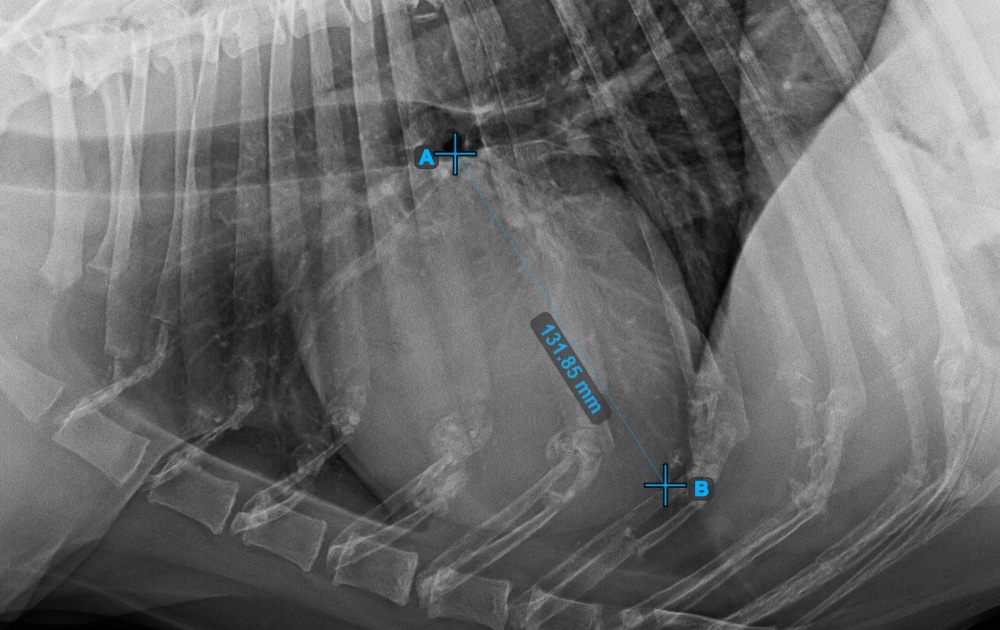

Start the measurement by marking the Bifurcatio tracheae, near the top of the heart.

The image below represents a typical placement of the Bifurcatio tracheae point.

Complete the long axis of the heart by marking the Apex point, near the bottom of the heart.

The image below represents a typical placement of the Apex point.